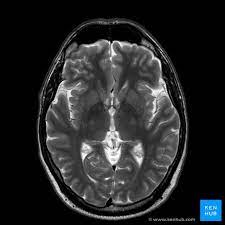

Riya's headaches became more frequent and intense, affecting her work productivity and quality of life. She realized it was time to seek medical advice. Her physician, Dr. Mehta, suggested a brain MRI—an advanced imaging technique that provides detailed images of the brain to detect any abnormalities. Riya was apprehensive about the procedure, worried about what it might reveal and its implications. However, Dr. Mehta reassured her that an MRI is a non-invasive and crucial diagnostic tool that would provide clarity and direction for her treatment.

One major problem faced by individuals like Riya is the uncertainty and anxiety stemming from unexplained health issues. The emotional burden of not knowing what is wrong can be overwhelming, leading to stress and fear. A brain MRI can solve this problem by offering a clear, detailed view of the brain's structure, helping to identify conditions such as tumors, strokes, or multiple sclerosis, and thus facilitating early intervention.

Riya's MRI results revealed a small benign tumor, a diagnosis that initially frightened her but also brought relief—knowing the cause of her symptoms was the first step towards effective treatment. Dr. Mehta explained that the tumor was treatable and not life-threatening, and with the right care, she could manage her symptoms and lead a normal life.